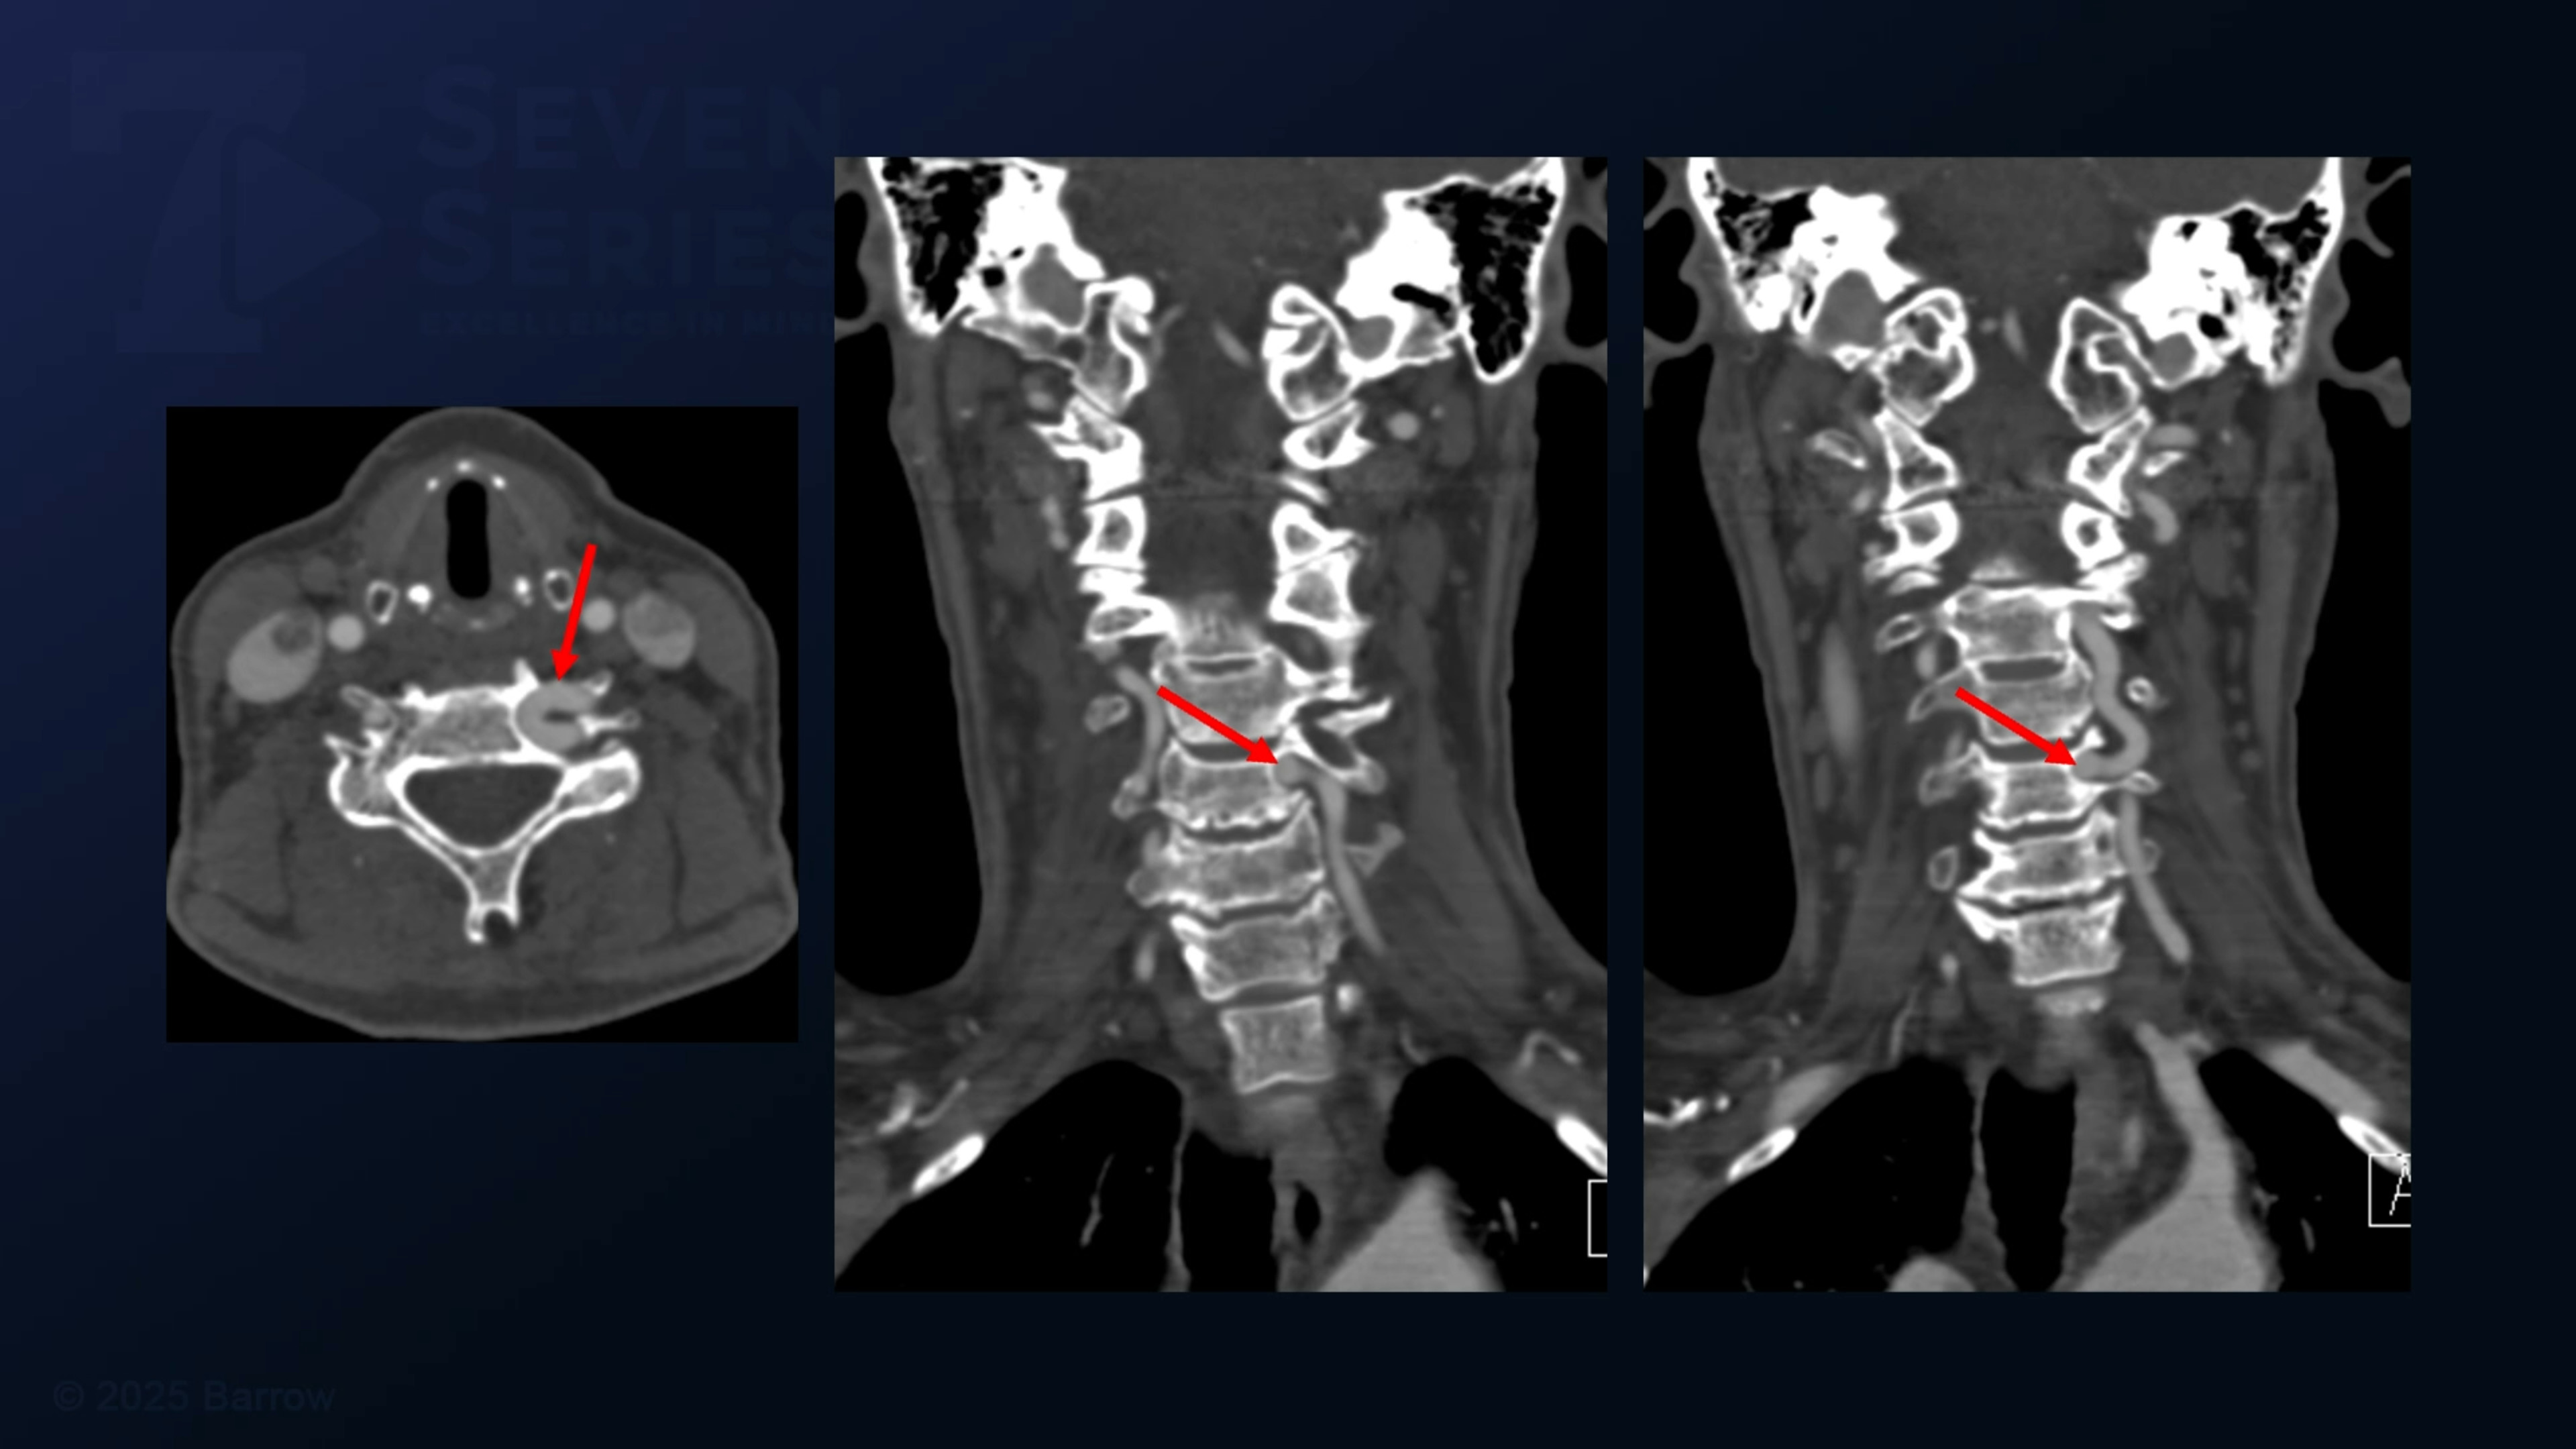

#474: V2 Vertebral Artery Dissection and Transposition with Decompression of the C5 Cervical Nerve Root

Episode 474 of Seven Series shows a V2 vertebral artery dissection and transposition with decompression of the C5 cervical nerve root.